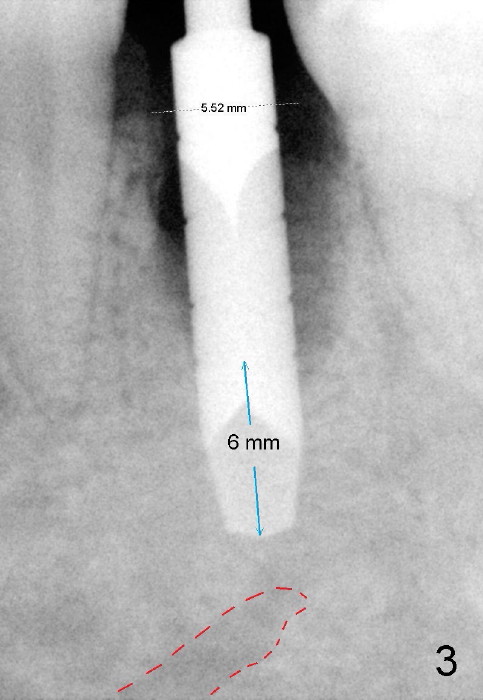

To avoid injury to the mental loop (Fig.2 dashed line), the depth of initial osteotomy is tightly controlled apical to the bottom of the socke.  Accurate measuring is the 2nd important measure to assure no or minimal neurological trauma. The wide socket (due to infection) allows to place an implant as wide as 7 mm.

Taking multiple intraop X-ray is also necessary for depth adjustment (Fig.3-5).  For example, when a 5x20 mm tap is inserted at the depth of 17 mm, it is close to the mental loop (Fig.4), whereas the binding to the bone is minimal.  So a larger implant is to be placed at a shallower depth (Fig.5: 6x17 mm with insertion torque >60 Ncm).  The shallower implant placement creates limited space for future abutment and crown (Fig.6,7).  A short abutment will be used and the implant margin will be prepared as low as possible.  As expected, the wound heals in a week (Fig.8).